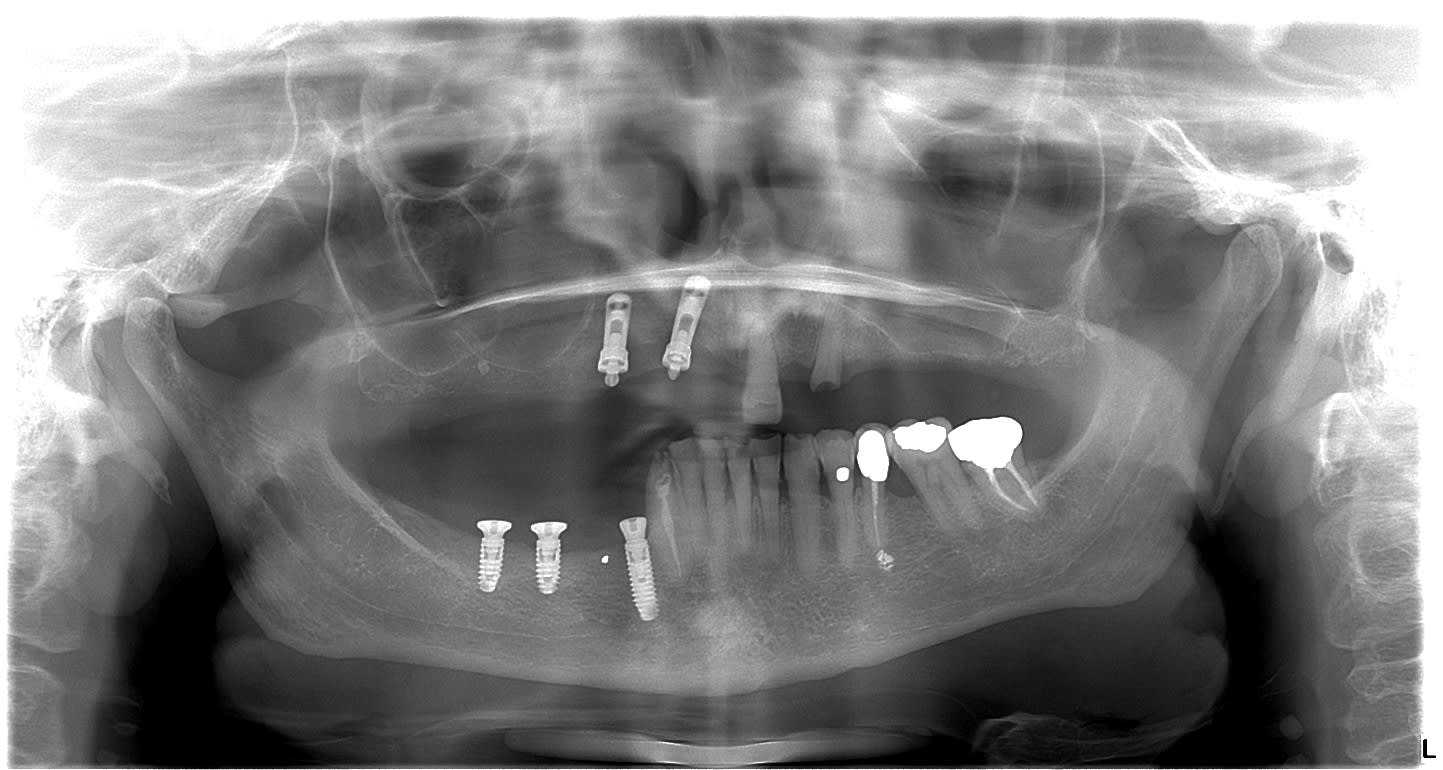

Pouvez vous me donner votre avis sur ces deux implants?

J'étais parti sur de L'imz mais le commercial me dit que non. Pensez vous que ca pourrait etre du calcitec distribué par Zimmer?

un calcitec c'est fort probable...ou alors un spline reliance là aussi de chez zimmer